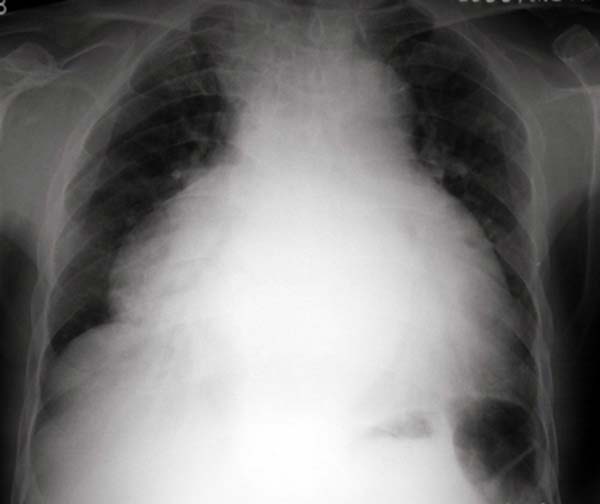

以下是引用jiangjing在2006-7-27 20:15:00的发言:[br]普大型心,目前片上难以确定肺血改变。可考虑 1.扩张型心肌病 2冠心病 3.心包积液。[均伴心功能不全]

以下是引用zhw974247在2006-7-26 21:17:00的发言:[br]普大型心,考虑 1.扩张型心肌病 2.联合瓣膜病 3.心包积液

以下是引用shilong在2006-7-26 22:20:00的发言:[br]这是一个典型的烧瓶样的心影,因其心影轮廓失去正常形态,应考虑心包积液